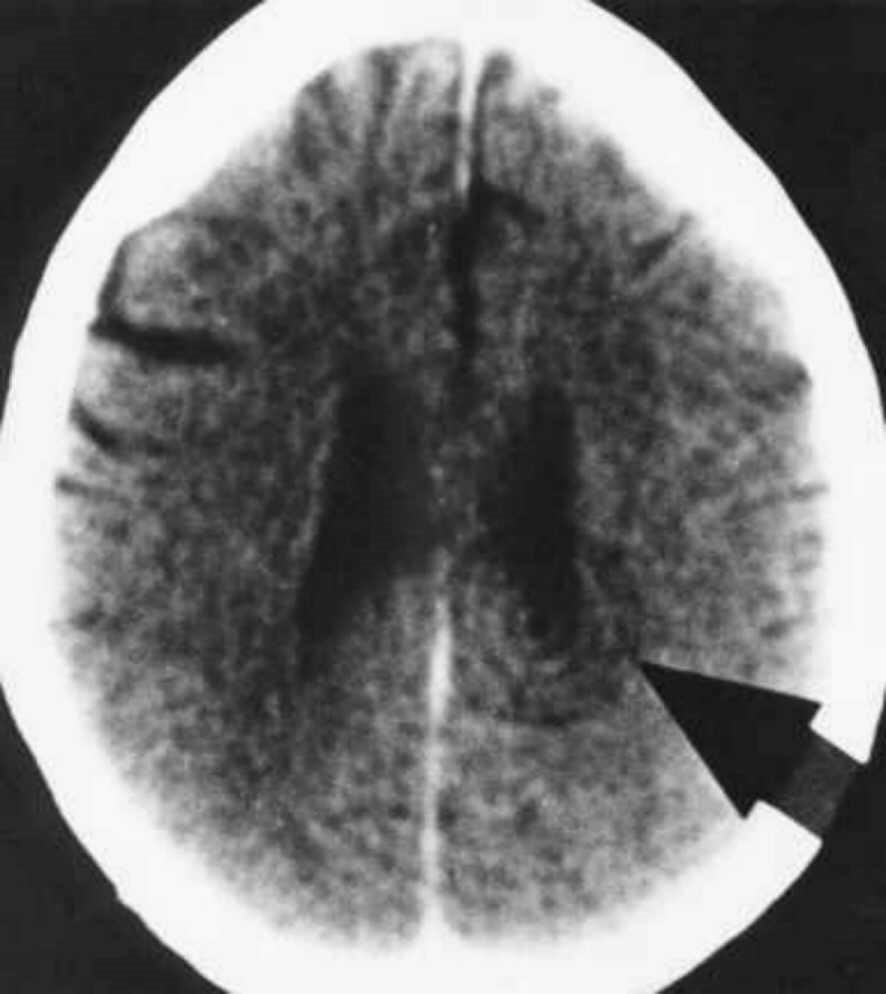

Beim DHS wird das zuständige Relaiszentrum im Gehirn markiert, d.h. es bilden sich scharfe Kreise, wir sagen auch konzentrische Kreise, die wie Schießscheiben aussehen.

Dabei ergibt sich die Stelle nicht zufällig, sondern sie ist das Computer-Relais, das das Individuum in der Sekunde des DHS dem Konfliktinhalt entsprechend „assoziiert“. Von diesem Hamerschen Herd aus wird wiederum in eben der gleichen Sekunde des DHS das mit dem HH korrelierende Organ von Krebs betroffen.

Sobald wir also in einem bestimmten Relais diese Schießscheiben-Konfiguration im CCT sehen, wissen wir, daß in diesem Relais ein Sonderprogramm läuft, d.h. der Organismus wurde in diesem Konflikt-, Gehirn- und Organbereich „auf dem falschen Fuß erwischt“ und hat ein Sonderprogramm eingeschaltet.

Im Gehirn haben beide Phasen natürlich ihren HH an der gleichen Stelle, allerdings in unterschiedlichem Zustand: In der konflikt-aktiven Phase stets mit scharf markierten Kreisen als sog. Schießscheibenkonfiguration, und in der konflikt-gelösten Phase ist der Hamersche Herd aufgequollen, oedematisiert. Das Oedem des innersten Ringes bezeichnen wir als „intrafocales Oedem“, das Oedem um den äußeren Ring als „perifocales Oedem“.